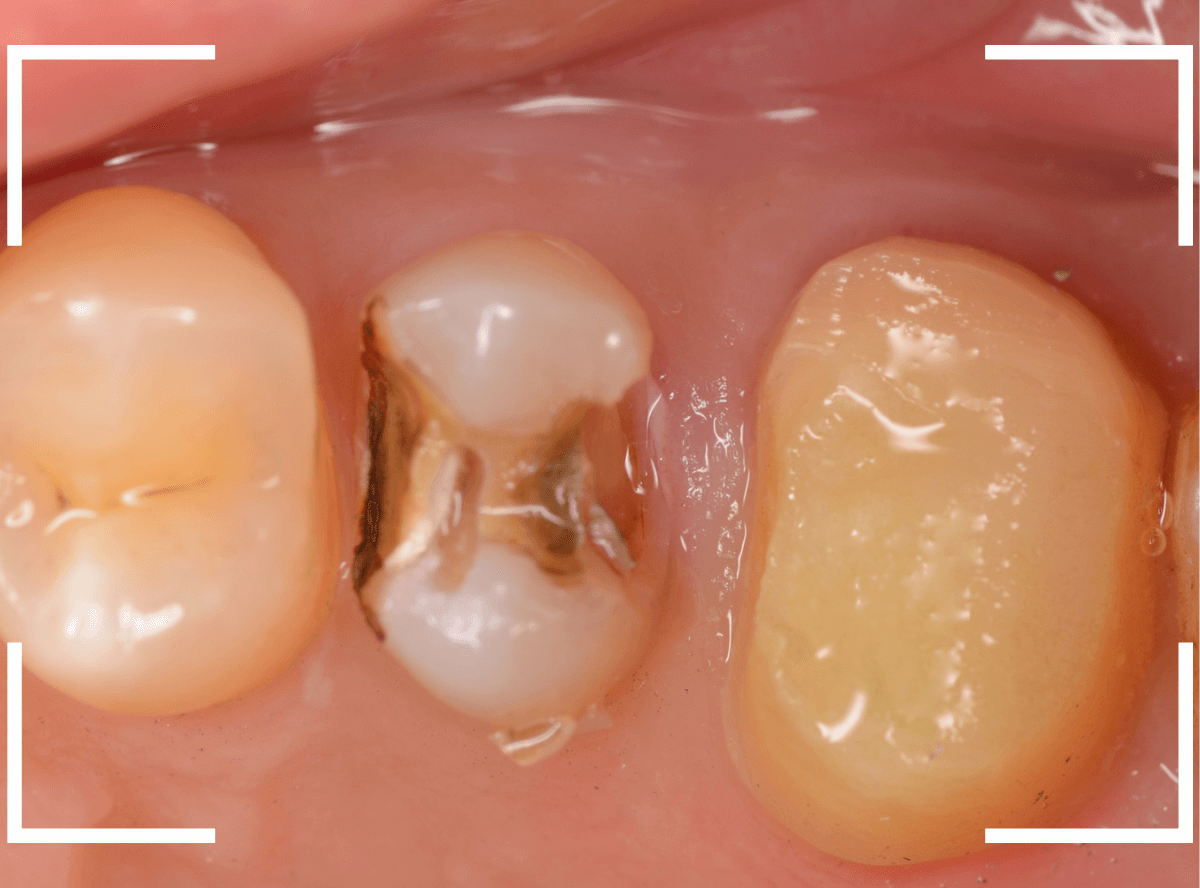

まずは、奥のメタル・クラウンを外します。

メタル・コアが入っていますが、こちらも慎重に外して、中を調べていきます。

レントゲン写真では問題なさそうでしたが、メタルコアを除去すると、中は真っ黒でした。

このように、コアの中で虫歯が進行している場合もありますので、さし歯をやり直す際は、出来る限りコアも外して調べるようにしています。

虫歯を全て除去しました。

幸い、あまり多く削る事なく進められたので良かったです。